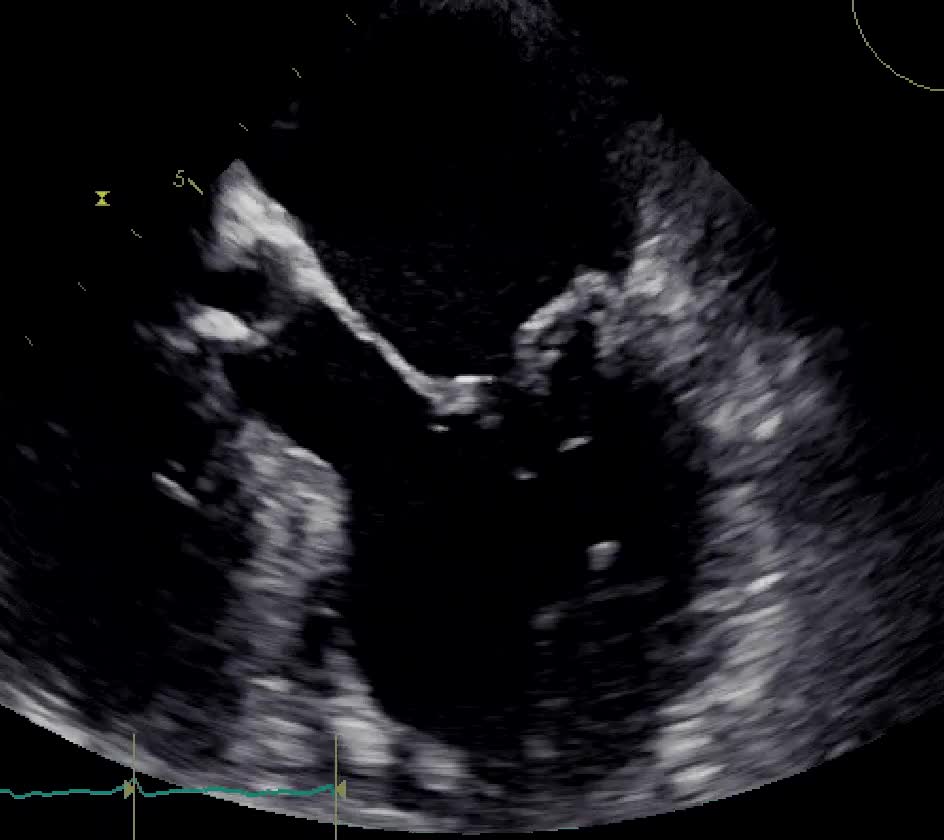

Insufficienza mitralica da rottura cordale

Autore:

Daniela Torta